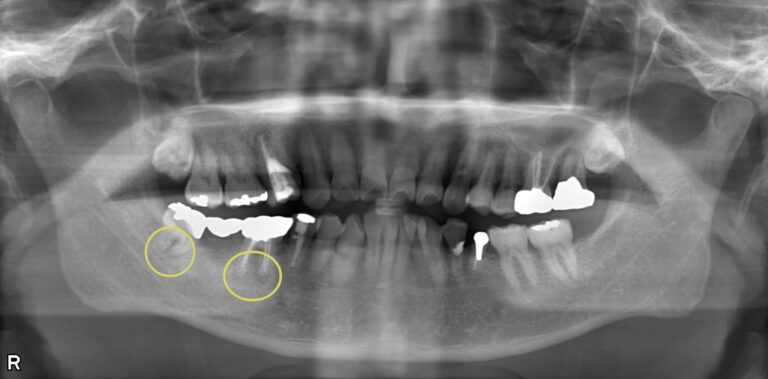

| 歯科用CTによる三次元診断 | 拡大ルーペの使用 |

| 一般的なレントゲン(二次元)では見えない、歯根の複雑な構造や病巣の位置を立体的に正確に把握し、治療の見落としを防ぎます。 | 肉眼では困難な根管内の細部を約8倍に拡大して確認し、処置の精度を高めます。 |

| 歯科用CTによる三次元診断 |

| 一般的なレントゲン(二次元)では見えない、歯根の複雑な構造や病巣の位置を立体的に正確に把握し、治療の見落としを防ぎます。 |